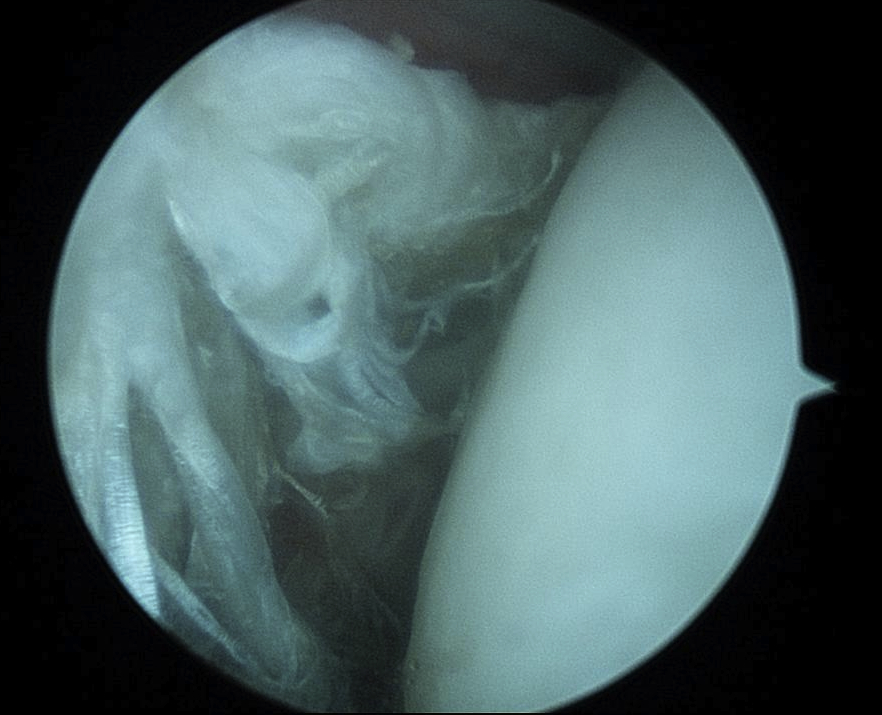

Arthroscopy

Normal

Tendonopathy

Medial subluxation of LHB